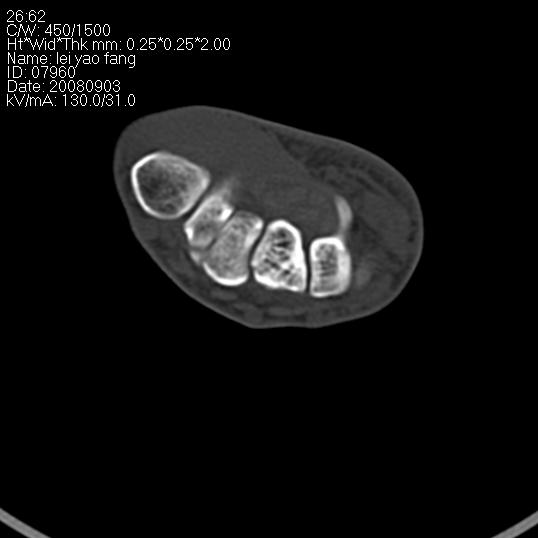

以下是引用杀毒软件在2008-9-4 17:41:00的发言:[br]考虑----舟骨囊肿